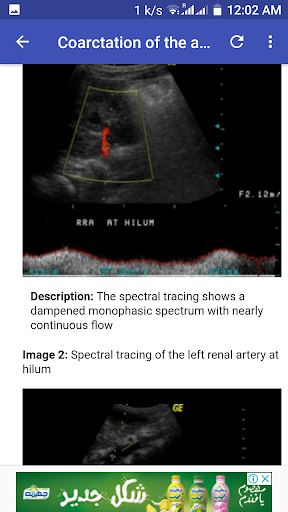

Le prime app ad ultrasuoni che comprendono un intero esame ad ultrasuoni con casi e immagini di rifornimento patologico. Include anche il rapporto della diagnosi differenziale. Tutto il maggior numero di 200 casi di scansione ad ultrasuoni sono stati discussi tra la parte seguente:

THIS APPS IS MAINLY FOR MEDICAL STUDENTS FOR TEACHING AND LEARNING PURPOSE.

-- Ultrasound measurement of Organs, which will let you to have the normal values of most important organs examined by ultrasound and make it easy for you to memorised them. E.g Lenght, height, width, Volume of abdominal and pelvic organ.